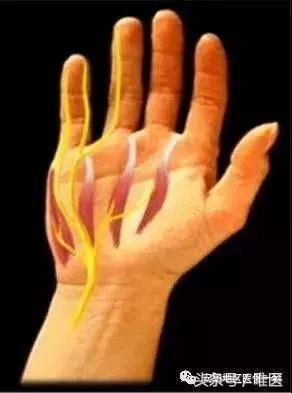

肘管綜合征是僅次於腕管綜合征的第二常見周圍神經卡壓綜合征,又稱遲發型尺神經炎,是尺神經在肘管內受壓引起的環指(尺側)、小指酸痛、麻木,肘部疼痛,手部內在肌肌力下降等症候群的病症。

肘管綜合征常見於體力勞動的中老年人,小指, 無名指感覺麻木、不適、疼痛,伸直無力,手指拿筷子不靈活,“虎口”處及掌骨間肌肉萎縮明顯。

嚴重者出現手部尺神經支配區域的運動功能障礙、感覺喪失,典型表現是爪形手畸形,因手部小肌肉萎縮而手掌凹陷,掌指關節過伸,指間關節屈曲,因食指、中指的蚓狀肌受正中神經支配,故手指屈曲畸形以環指、小指為著,拇指常處於外展狀態,手指分開、合並動作受限制,小指動作喪失。感覺喪失區主要在手背尺側,小魚際、小指和無名指的尺側一半。